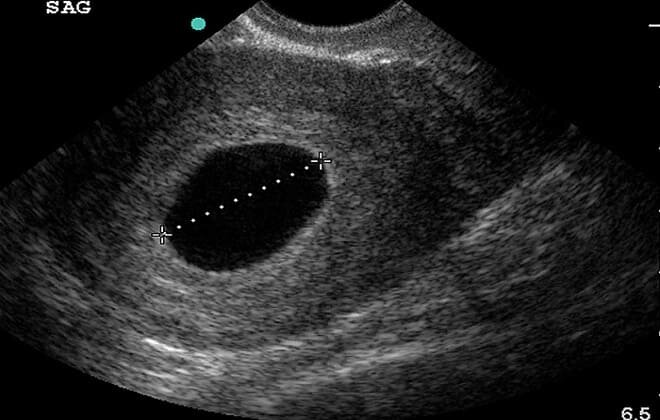

Если врач с помощью аппарата УЗИ не может точно сказать, жив ли зародыш по причине его нечеткой визуализации или из-за того, что он не сформировался, медицинская практика предусматривает проведение контрольных анализов на ХГЧ с 2-дневным интервалом. Пустота плодного яйца не сможет обеспечить удвоение показателей гормона каждые 2 дня, как это происходит в условиях беременности, развивающейся без осложнений в виде подобной патологии.

Подтвержденная анэмбриония влечет за собой необходимость проведения медикаментозного аборта или хирургического вмешательства с целью очищения полости матки от пустого хориона. Поэтому замедленный рост ХГЧ не может стать основанием для прерывания беременности. Только после 2-3 процедур ультразвуковых исследований предположительный диагноз может быть подтвержден окончательно.